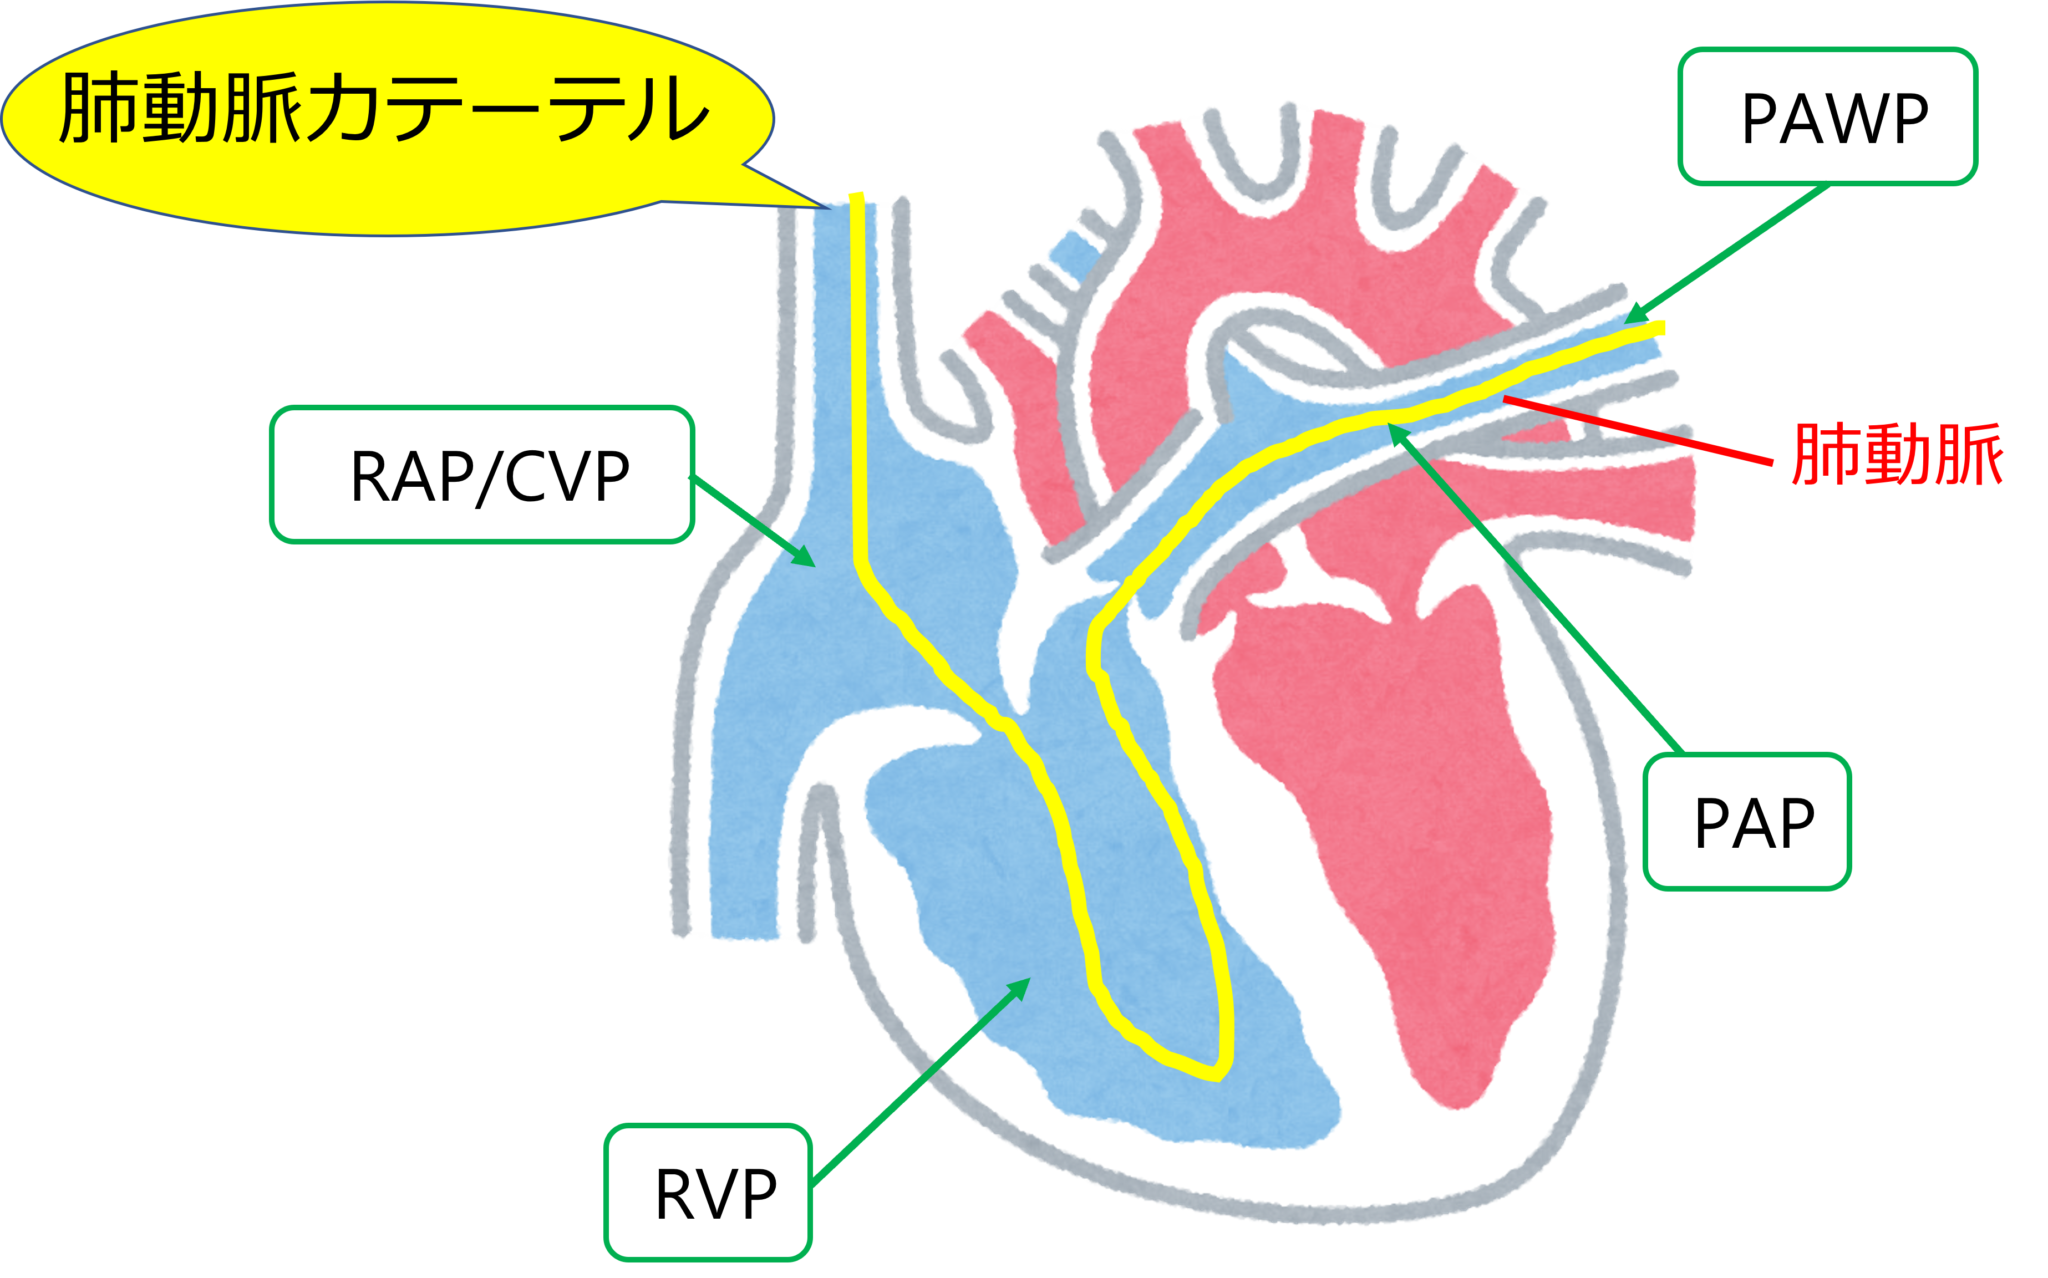

この手順では、肺動脈カテーテル (PAC) を心臓の右側と肺につながる動脈に挿入します。 PAC にはバルーンチップが付いています。バルーンを使用すると、カテーテルを血液の流れに乗って心臓内の使用場所まで運ぶことができます。

この処置自体は、右心カテーテル法と呼ばれることもあります。これは、心臓の右側を流れる血液の圧力を測定できるためです。 3 つの異なる場所で圧力を測定します。

- 右心房

- 肺動脈

- 肺毛細血管

これらの測定値は、心臓の適切な部分の血液中の酸素量を把握するために使用できます。また、心臓から全体的にどれだけの血液が流出するかを把握するためにも使用されます。

スワンガンツカテーテル法では、PAC がこれらのアクセス ポイントの 1 つに挿入され、右心と肺の血管と部屋に誘導されます。